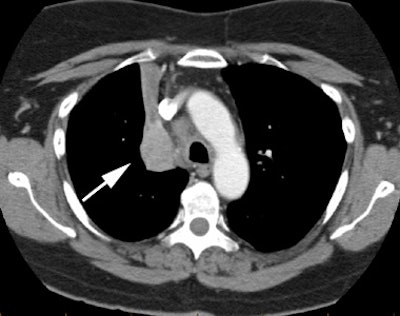

CT imaging confirmed a right upper lobe collapse with a central mass (white arrow). The lesion was hot on PET imaging (black arrow) and there was also uptake within pathologic mediastinal lymph nodes. The lesion proved to be a non-small cell lung cancer.  |